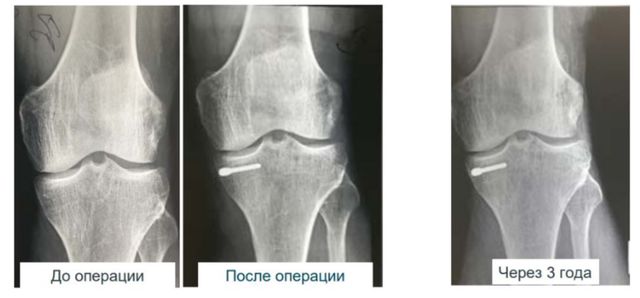

Клинические наблюдения демонстрируют высокую эффективность метода. Приведем несколько примеров из практики.

Пациент 65 лет поступил с выраженным болевым синдромом. После имплантации ортопедического электрета через 9 месяцев было зафиксировано полное отсутствие болевого синдрома и признаков прогрессирования дегенеративных изменений.

Пациент 65 лет с тяжелой формой остеоартроза. Через 3 года после установки электрета отмечаются сохранение положительного эффекта, отсутствие боли, стабильность рентгенологической картины.